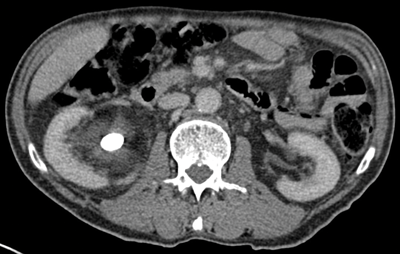

Filling defect

The collecting systems and ureters should be opacified on the excretory phase of CT urogram and adequate distension and opacification of the ureter and pelvicalyceal system are vital when evaluating the urothelium. Filling defects can be difficult to appreciate on abdominal windows and subtle filling defects are more clearly seen on bone window settings. This can allow ureteric neoplasms to be distinguished from other causes of filling defects. Figure 4 shows an example of a filling defect in the left ureter that is more clearly defined on bone windows compared with abdominal windows. This was a female patient who presented with cyclic pain and was found on biopsy to have endometriosis in the left ureter.

Figure 4a: Abdominal windows filling defect.

Figure 4b: Bone windows filling defect.